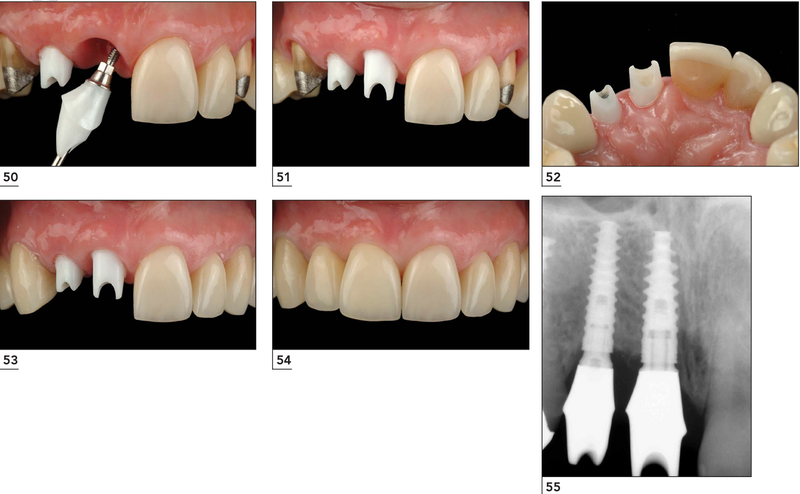

4. Quy trình đặt mão răng sứ trên Implant

Sau khoảng 3 tháng từ khi cấy trụ Implant, bác sĩ sẽ tiến hành lấy dấu hàm để thiết kế trụ phục hình cá nhân hóa và mão răng sứ phù hợp. Khoảng 3 - 5 ngày sau, mão răng sứ sẽ được hoàn thiện và sẵn sàng để lắp đặt.

Quy trình lắp mão răng sứ diễn ra trong khoảng 30 phút - 1 tiếng, gồm các bước sau:

• Đặt trụ phục hình cá nhân hóa: Trụ này giúp kết nối chặt chẽ giữa mão răng sứ và trụ Implant.

• Lắp mão răng sứ: Bác sĩ cố định mão sứ lên trụ phục hình, đảm bảo khớp với răng tự nhiên.

• Điều chỉnh lực nhai: Kiểm tra độ chịu lực của răng sứ để đảm bảo ăn nhai ổn định.

• Thử khớp cắn và siết lực: Đảm bảo mão răng sứ không gây cộm cấn, ăn nhai thoải mái.

• Bịt lỗ kỹ thuật: Kết thúc quá trình lắp răng, giúp mão sứ chắc chắn và thẩm mỹ hơn.

Toàn bộ quá trình diễn ra nhẹ nhàng, không đau, chỉ có cảm giác hơi nén lợi nhưng sẽ hết ngay sau khi lắp răng hoàn tất. Cô chú/anh chị có thể ăn nhai gần như bình thường ngay sau khi lắp mão răng sứ.